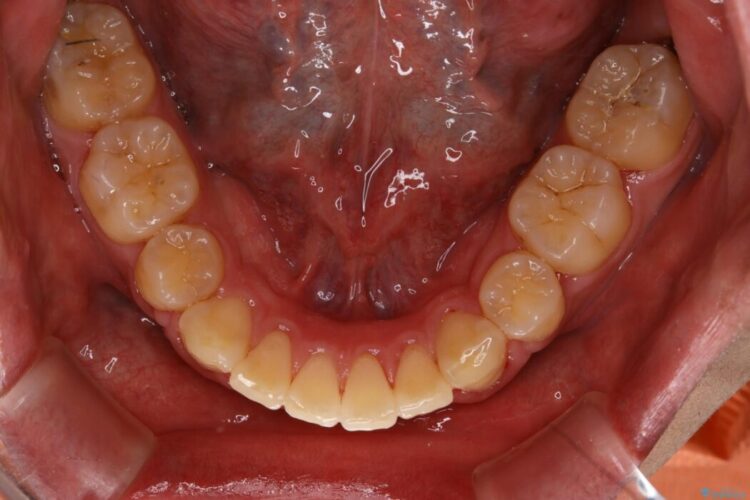

上の歯の出っ歯と下の歯のガタつきが気になるとご来院された患者様です。

出っ歯とガタつきの改善には抜歯が必要と診断し、上下左右第一小臼歯を抜歯することとしました。